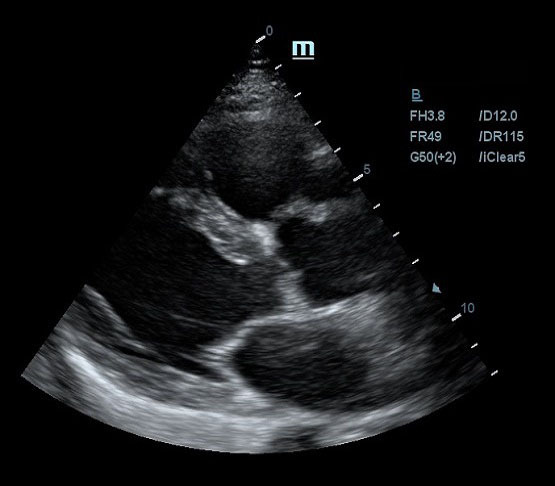

УЗ-сканер Mindray M5 представляет собой полнофункциональную портативную, размером с ноутбук, систему цветной допплерографии, обеспечивающую безупречную визуализацию в формате 2D и оптимальное соотношение цены и качества при очень удобной и простой в использовании комплектации. Оснащенная специализированными технологиями, удовлетворяющими широкий спектр потребностей врачей-ветеринаров, система М5 является оптимальным вариантом для применения в различных клинических условиях.

Изолированная гармоническая визуализация для улучшения контрастного разрешения, обеспечивающая более четкое изображение с превосходным пространственным разрешением и меньшим уровнем шума.

Позволяет использовать несколько углов сканирования для формирования единого изображения, что приводит к увеличению контрастного разрешения и улучшению визуализации.

Позволяет улучшить качество изображения, основываясь на автоматическом распознавании структур.

- Более четкие края и контуры

- Плавное и однородное отображение тканей

- Снижение зернистости в «областях без эхосигнала»